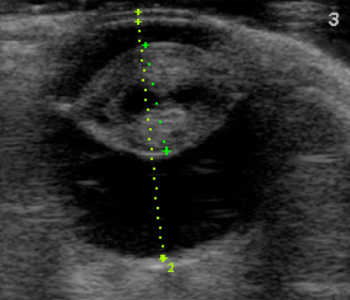

【超音波(エコー)検査】

目の中、特に硝子体や網膜など水晶体の裏側がどのような状態なのか調べます。エコー検査により、白内障の混濁状態や網膜剥離や眼内出血などの合併症の評価を行います。

白内障(成熟)